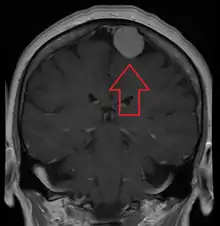

Meningiomas are visualized readily with contrast CT, MRI with gadolinium,[22] and arteriography, all attributed to the fact that meningiomas are extra-axial and vascularized. CSF protein levels are usually found to be elevated when lumbar puncture is used to obtain spinal fluid. On T1-weighted contrast-enhanced MRI, they may show a typical dural tail sign absent in some rare forms of meningiomas.[17]